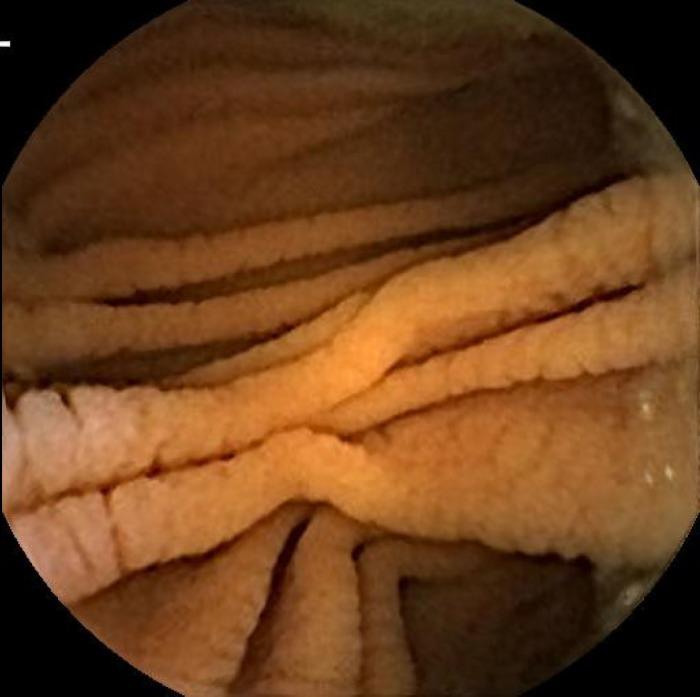

Intestinal pseudo-obstruction (IPO) is a rare complication of celiac disease (CD) and has often resulted in laparotomy for diagnosis. We report an adult case of CD presenting as IPO with severe protein calorie malnutrition (PCM) and negative endomysial as well as tissue transglutaminase antibodies. This is the first case report of CD presenting with combined IPO, severe PCM, negative first-line celiac serologies, and terminal ileal atrophy that was diagnosed without laparotomy. A non-surgical diagnosis was achieved by expanded laboratory and endoscopic methods, including video capsule endoscopy. Extent of pathologic gut involvement and response to treatment with budesonide and gluten-free diet is described.